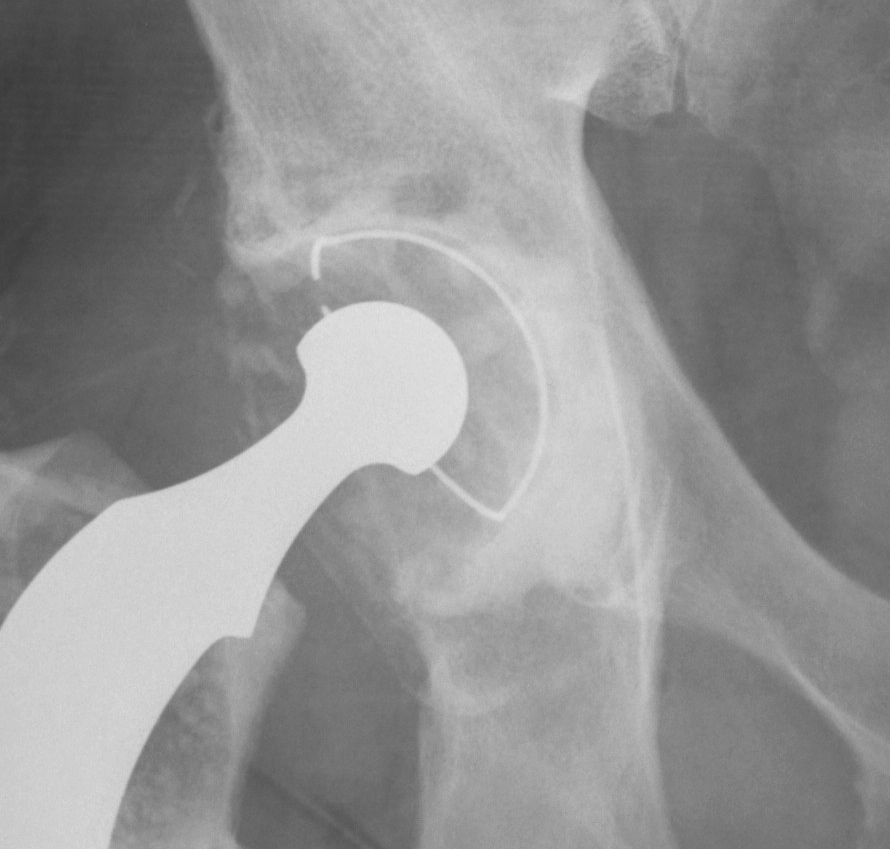

Paprosky Type I, II A and B

I Rim intact

II A Mild superior migration / superior rim intact

II B < 30% superior rim missing

1. Uncemented Jumbo rim fit cup

Indications

- > 50% host bone available for ingrowth

- > 2/3 rim intact

Technique

- implant in usual position

- preferentially ream anteriorly

- preserve posterior column

- some uncovering superiorly allowed

- usually augment with screws

- +/- postoperatively NWB 6/52

Results

- 12-15 year survival between 81-96%